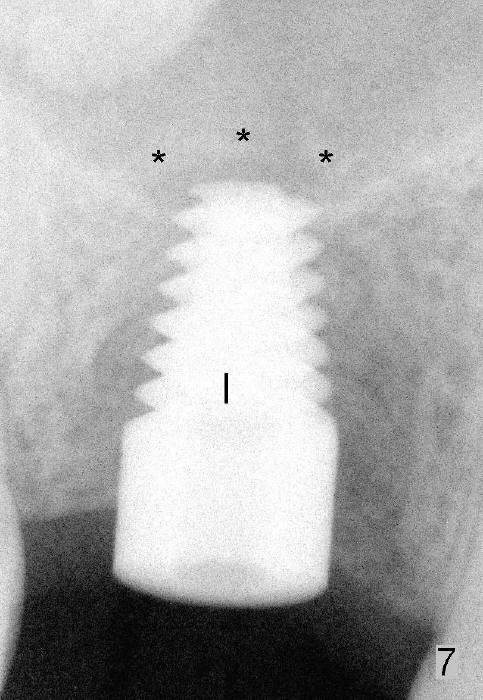

Six months and a half later, the socket appears to be empty (Fig.5) with apparently buccal plate collapse (as indicated by inset in Fig.5). The bony ridge is measured to be ~ 5 mm buccolingually using bone gauge. Osteotomy forms by bone expansion technique. In short, #15 blade is used to split the ridge (slightly lingual), followed by bone scalpels 4,5, and 6 mm, bone blades 4, 5.5 and 7.5 mm, and round tapered osteotomes 2, 3, 4 and 5 mm (Tatum Surgical). The depth is approximately 11 mm. When the last osteotome (4.5 mm round blunt) is used, it deviates too much lingually. A surgical curet is used to explore the osteotomy site. The bony wall appears to be intact except lingual. A 6x11 mm tapered tap is inserted with some resistance (Fig.6). In contrast it is difficult to engage 5.8 mm round tap into the osteotomy site. A 6x11 mm tapered implant is placed with insertion torque 40 Ncm (Fig.7). Amoxicillin is prescribed. The patient is doing fine postop, although the implant is not stable with mild tenderness. Six month post-implantation, the implant appears to have been descended (Fig.8,9, compare to Fig.7).